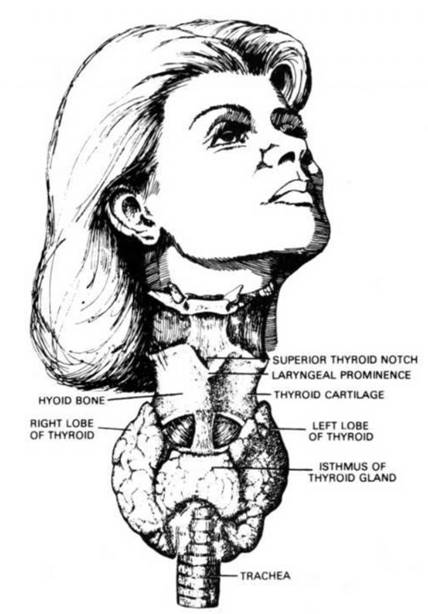

11. TheThyroid Gland, one of the most vital and important glands of the body. It requires Iodine-foods for proper functioning. When improperly nourished causes Goiter.

THE THYROID GLAND